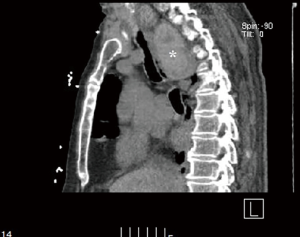

Institutional review board exemption was obtained prior to commencing this study (IRB 2014-12-15). Consent from the patient was not required because the information is recorded by the investigator in such a manner that research participants cannot be identified, directly or through identifiers linked to the research participant. Between 2012 and 2015, 280 thyroidectomies were performed of which 45 (16%) had a retrosternal component. Thirty-nine out of 45 (86%) retrosternal goiters were anterior mediastinal, only one of which required thoracoscopy. Six of 45 (13%) were middle/posterior mediastinal. Out of 7 retrosternal goiter that required thoracoscopic approach, 1 was anterior mediastinal and 6 were middle/posterior mediastinal. Seven patients with large mediastinal goiters, particularly those with atypical mediastinal extension (paratracheal, retroesophageal, etc.) were evaluated by a thoracic surgeon preoperatively and selected for simultaneous unilateral thoracoscopy and cervical thyroidectomy (Table 1, Figures 1,2) . Patient age range was 57 to 91. Six of the patients were female. Only one of the patients had clinical hyperthyroidism while the remainder of patients was euthyroid. Two patients had goiters that extended into the right paratracheal region, two patients had goiter extension to the left paratracheal/subaortic region, one patient had goiter extension to the retrotracheal region and one patient had extension of the left thyroid lobe to the right hemithorax via the retroesophageal plane. The last patient had a large substernal calcified thyroid goiter extending from the left lobe. Seven patients had respiratory symptoms with stridor and tracheomalacia. Two patients required perioperative mechanical ventilation and one required an emergency tracheostomy on presentation. The patient with a retroesophageal goiter also had symptoms of dysphagia. The patient with clinical hyperthyroidism presented with new onset atrial fibrillation. None of the patients had malignancy. All patients underwent preoperative stabilization prior to elective resection.